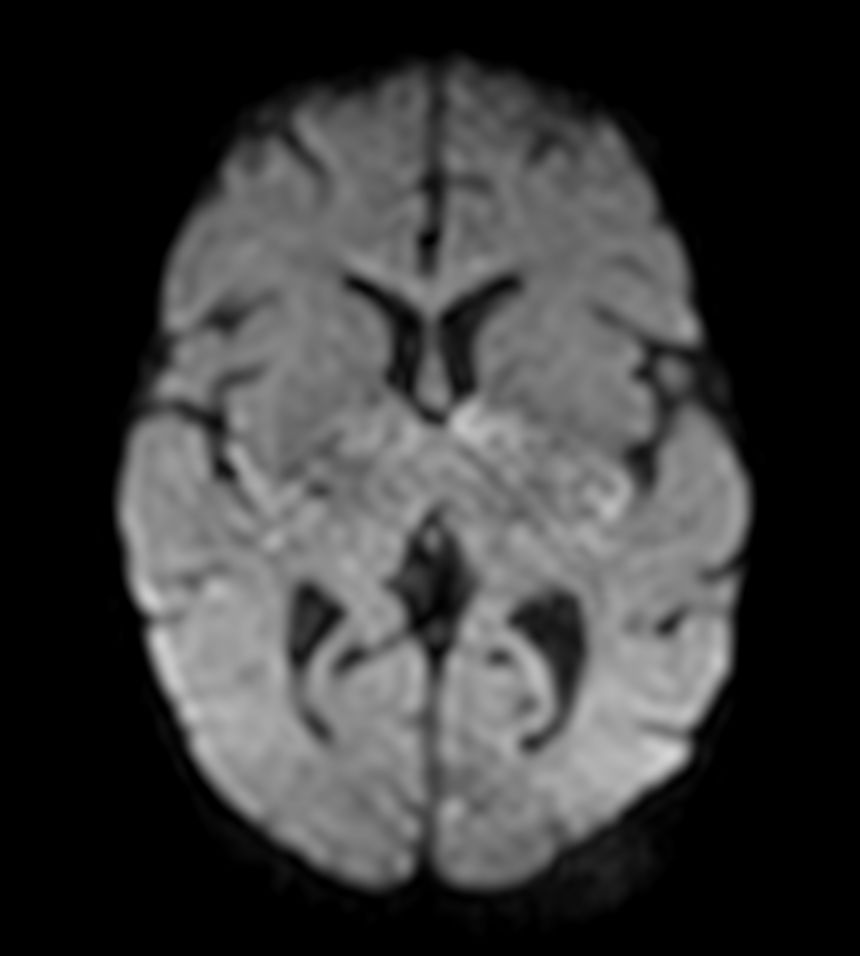

Axial DWI (b1000) with ComforTone